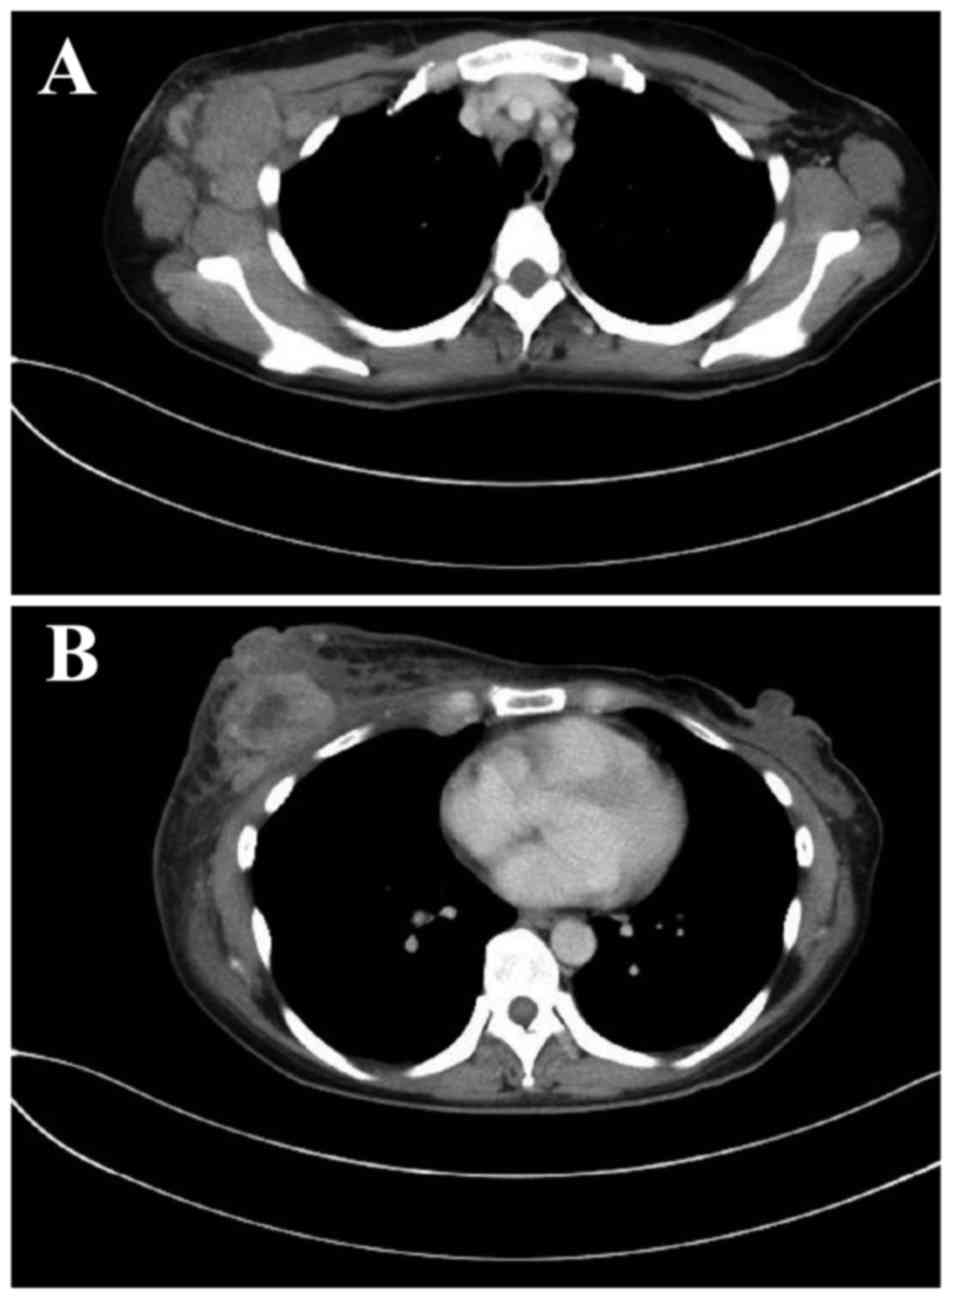

A 42-year-old woman with carcinoma of the right breast (T4N3aM0, stage IIIC) underwent mastectomy and level III axillary lymph node dissection (Fig. 1).

Figure 1.

Contrast-enhanced computed tomography examination prior to therapy revealed (A) metastasis to the axillary lymph nodes and (B) skin invasion by the tumor cells.